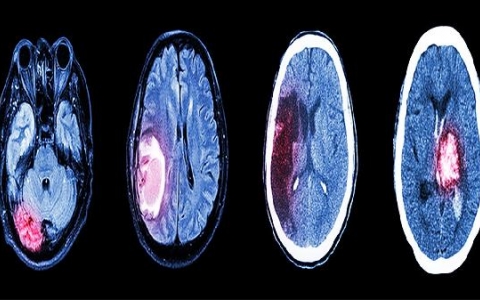

如何治疗颅脑损伤

如何治疗颅脑损伤?颅脑损伤根据情况不同,颅脑损伤症状较严重,患者常有更明显的脑挫伤血肿会出现昏迷、意识障碍、颅骨骨折、脑出血和颅内高压导致脑缺血,进一步导致继发